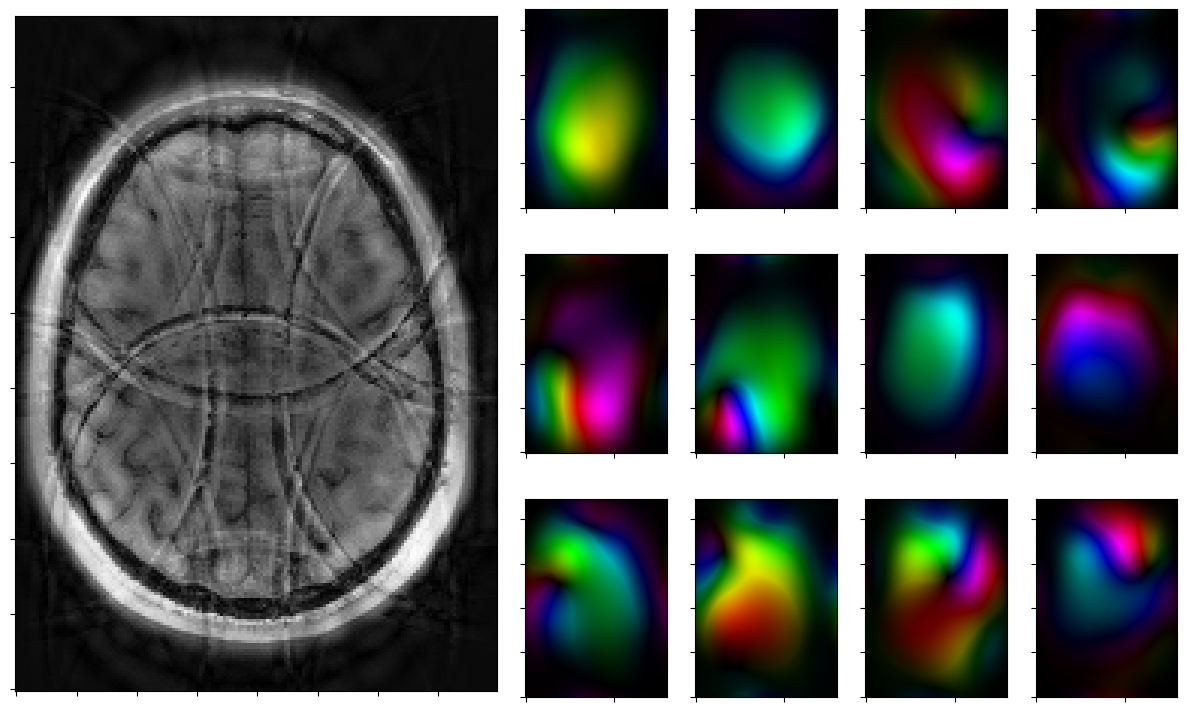

Run solver by hand and plot iterates

Run the solver iteratively and plot each step.

[12]:

for reco, reco_data in solver.while_(stoprule):

rho, coils = smoother.codomain.split(smoother(reco))

#rho, coils = normalize(rho,coils)

fig = plt.figure(figsize = (15,9))

gs = fig.add_gridspec(3,7)

axs = [fig.add_subplot(gs[0:3, 0:3])]

axs[0].imshow(np.abs(rho),cmap=mplib.colormaps['Greys_r'],origin='lower')

axs[0].xaxis.set_ticklabels([])

axs[0].yaxis.set_ticklabels([])

for j in range(3):

for k in range(3,7):

axs.append(fig.add_subplot(gs[j,k]))

axs[-1].xaxis.set_ticklabels([])

axs[-1].yaxis.set_ticklabels([])

for j in range(nrcoils):

axs[1+j].imshow(complex_to_rgb(coils[j,:,:]),origin='lower')

plt.show()

2026-01-29 15:10:11,564 INFO     CountIterations      :: it. 2>=5

2026-01-29 15:10:11,729 INFO     CombineRules         :: it. 0>=1000 | ((rel X:--(x=0)! | rel Y:--(y=0) ) & kappa:1.0e+00) | it. 0>=1000

2026-01-29 15:10:11,909 INFO     CombineRules         :: it. 1>=1000 | ((rel X:3.6e+01>=2.5e-01  | rel Y:2.5e+00>=2.5e-01 ) & kappa:1.0e+00) | it. 1>=1000

2026-01-29 15:10:12,064 INFO     CombineRules         :: it. 2>=1000 | ((rel X:1.6e+01>=2.5e-01  | rel Y:1.2e+00>=2.5e-01 ) & kappa:1.3e+00) | it. 2>=1000

2026-01-29 15:10:12,228 INFO     CombineRules         :: it. 3>=1000 | ((rel X:8.8e+00>=2.5e-01  | rel Y:7.0e-01>=2.5e-01 ) & kappa:1.6e+00) | it. 3>=1000

2026-01-29 15:10:12,415 INFO     CombineRules         :: it. 4>=1000 | ((rel X:5.9e+00>=2.5e-01  | rel Y:4.9e-01>=2.5e-01 ) & kappa:2.0e+00) | it. 4>=1000

2026-01-29 15:10:12,557 INFO     CombineRules         :: it. 5>=1000 | ((rel X:4.5e+00>=2.5e-01  | rel Y:4.0e-01>=2.5e-01 ) & kappa:3.0e+00) | it. 5>=1000

2026-01-29 15:10:12,735 INFO     CombineRules         :: it. 6>=1000 | ((rel X:3.5e+00>=2.5e-01  | rel Y:3.5e-01>=2.5e-01 ) & kappa:4.7e+00) | it. 6>=1000

2026-01-29 15:10:12,903 INFO     CombineRules         :: it. 7>=1000 | ((rel X:2.7e+00>=2.5e-01  | rel Y:3.1e-01>=2.5e-01 ) & kappa:5.0e+00) | it. 7>=1000

2026-01-29 15:10:13,052 INFO     CombineRules         :: it. 8>=1000 | ((rel X:2.1e+00>=2.5e-01  | rel Y:2.8e-01>=2.5e-01 ) & kappa:5.0e+00) | it. 8>=1000

2026-01-29 15:10:13,197 INFO     CombineRules         :: it. 9>=1000 | ((rel X:1.7e+00>=2.5e-01  | rel Y:2.5e-01>=2.5e-01 [Rule RelTolYStop(0.3333333333333333) triggered.]) & kappa:4.5e+00[All rules triggered.]) | it. 9>=1000

../_images/notebooks_parallel_mri_21_5.png